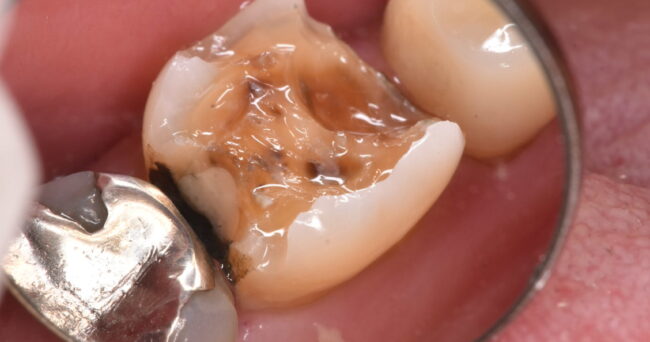

処置前写真、どこがどうなっているのか、よくわからない。とりあえずぐちゃぐちゃしたものがある、という印象だと思います。

ちなみにドクターはこの時点で、抜歯を考えます。どうしても抜きたくない!という場合は、あまりおすすめしないですが、神経をとって歯を残る治療ができるかを模索します。

大まかに悪い部分をとりました。「抜かなくてもよさそうじゃないか」という声が上がりそうですが、歯の半分近くが歯ぐきよりも下に埋まっているのが見えるでしょうか?